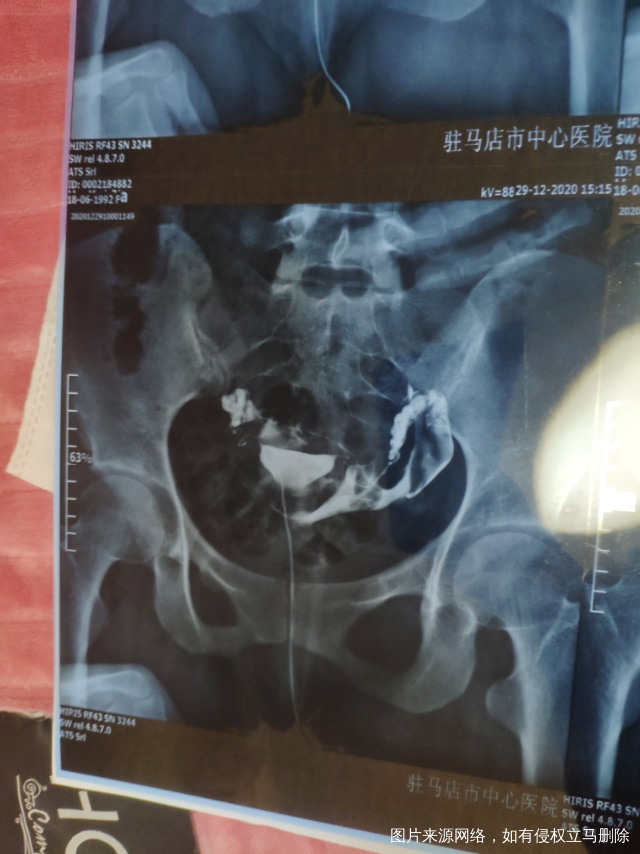

输卵管造影最近做的输卵管造影和之前做的腹腔镜

做完输卵管造影第六天了小腹还是感觉沉甸甸的如

可以热敷腹部,如果有发热,腹痛加剧,白带量多,有异味,随时就医